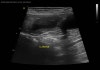

초음파 검사

수술전 복부 초음파검사 / 출처: 라온동물메디컬센터

초음파 검사에서 자궁 내부에 염증성 내용물이 차 있는 소견이 확인되었습니다.